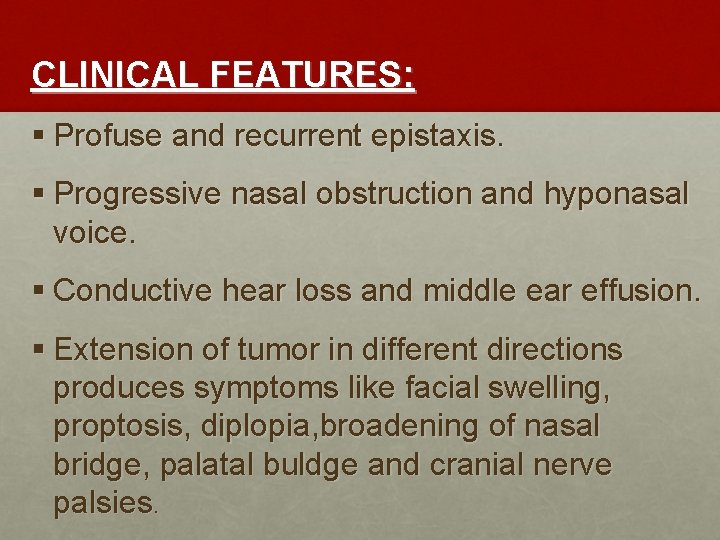

CLINICAL FEATURES: § Profuse and recurrent epistaxis. § Progressive nasal obstruction and hyponasal voice. § Conductive hear loss and middle ear effusion. § Extension of tumor in different directions produces symptoms like facial swelling, proptosis, diplopia, broadening of nasal bridge, palatal buldge and cranial nerve palsies.